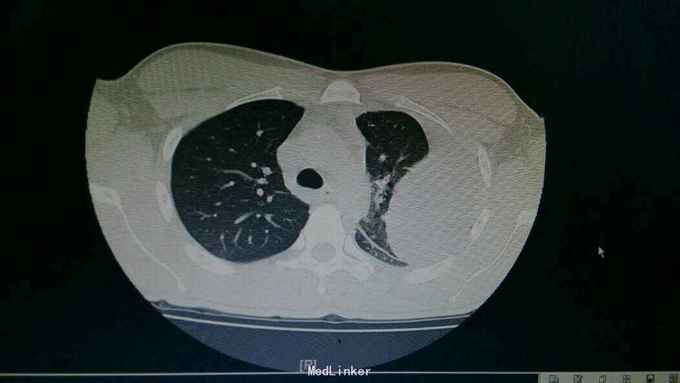

查体:神情,左侧呼吸运动减弱,叩诊浊音,左肺呼吸音低,右侧呼吸性正常。 辅查:胸部CT:左侧大量胸腔积液,左肺受压实变。复查胸片:左侧胸腔积液减前好转。胸水提示渗出性胸腔积液,淋巴细胞为主。T-SPOT:A:64个,B:42个。

诊断:结核性胸膜炎。 治疗:入院结合予以抗结核治疗,胸腔穿刺引流术。